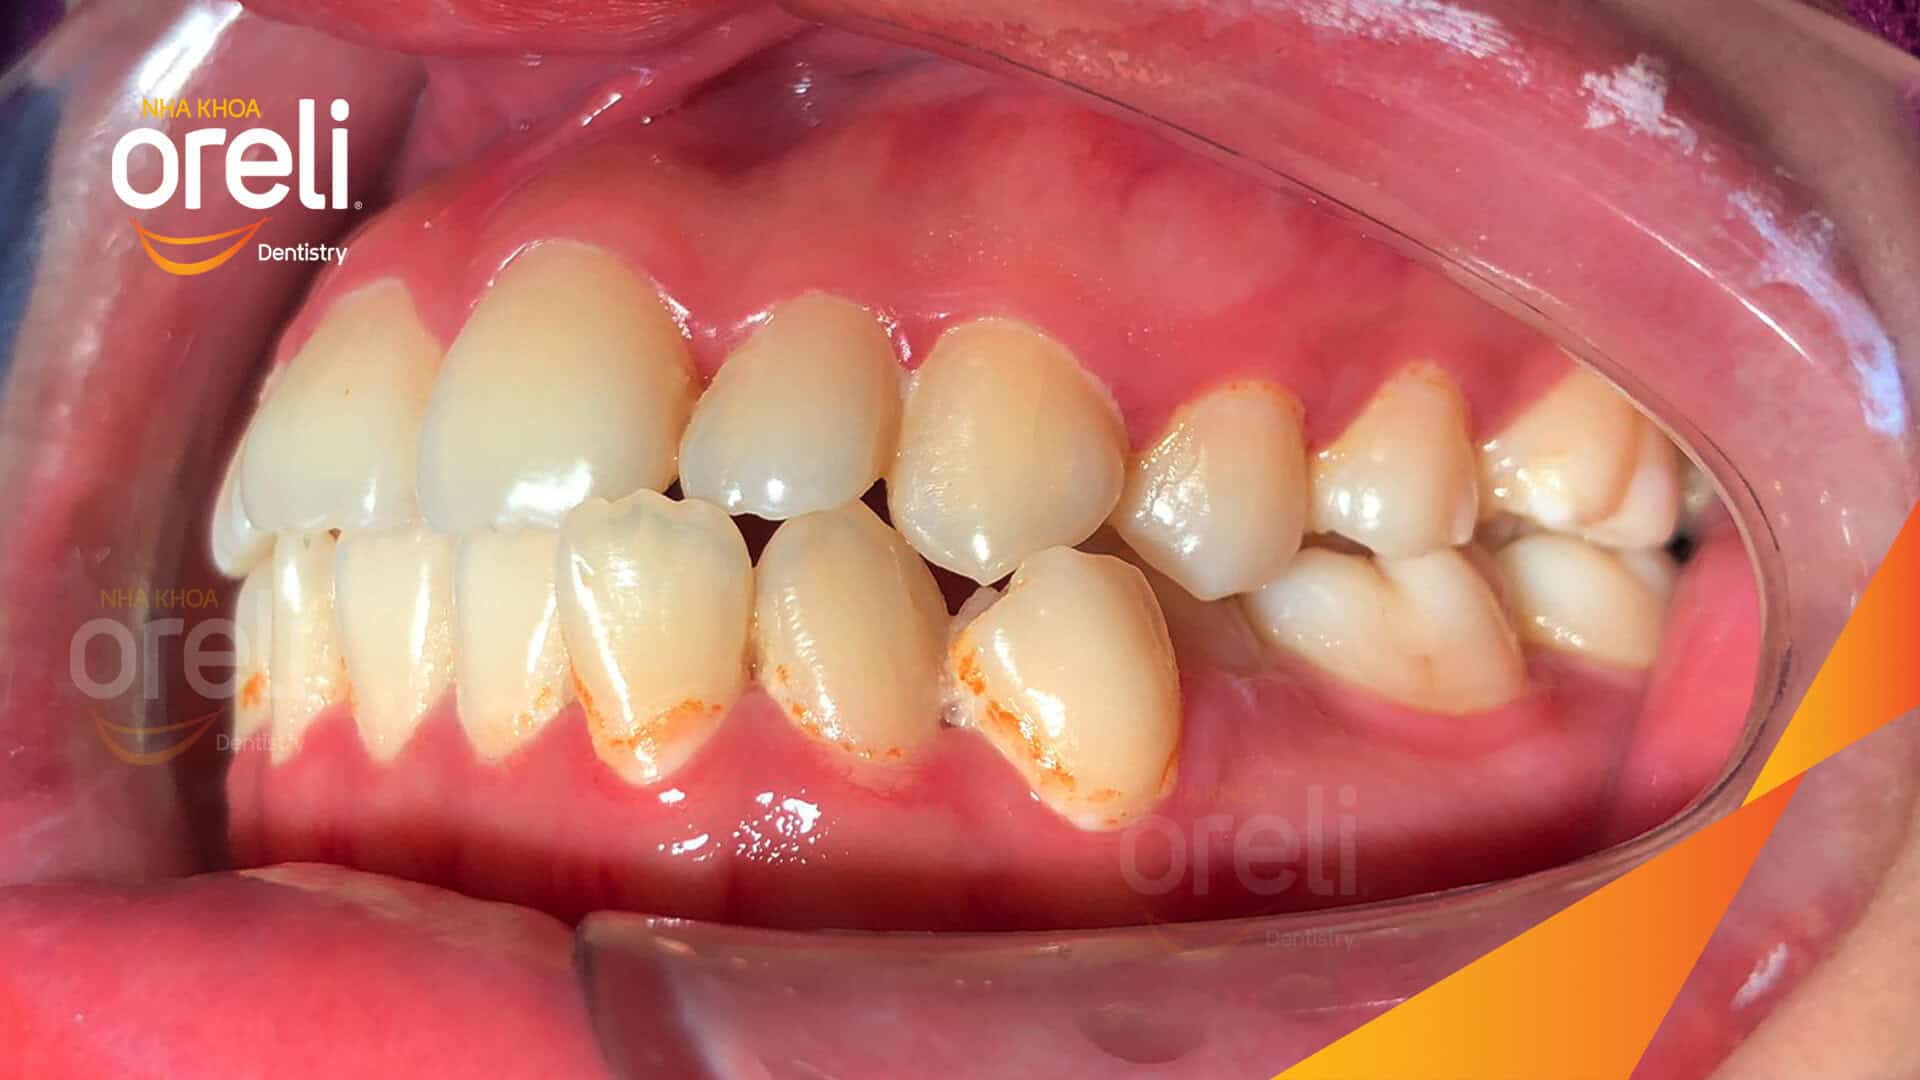

Ca niềng răng sai khớp cắn hạng 3 móm nặng có nhổ răng số 7 – Kết quả thực tế Niềng răngChỉnh lệch cằmMóm Xem thêm